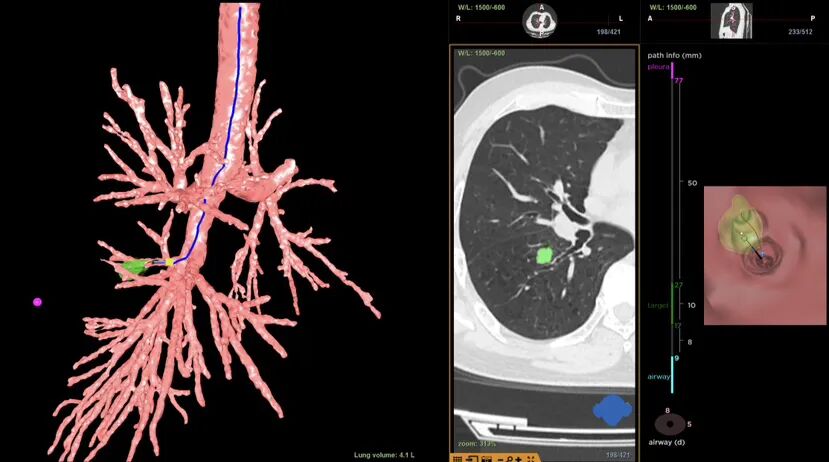

前Lung pro规划路径

术中C臂CT影像

术前,团队进行了充分的准备,用气道内的“GPS”虚拟导航系统(Lung pro)规划出抵达病灶的最优路径。

术中,团队在患者全麻插管状态下先行EBUS-TBNA,并通过现场细胞学评估排除淋巴结转移可能,同时取出组织送病理确诊,确认患者具有接受射频消融手术的指征。随后,团队使用细支气管镜经支气管建立肺实质抵达结节隧道,并经C臂CT及径向超声确认到达结节后,取材进行活检,经过现场细胞学评估结节为恶性细胞。组送病理再次确诊后,团队决定立即行射频消融,消融过程中利用C臂CT实时观察消融范围及探针位置。